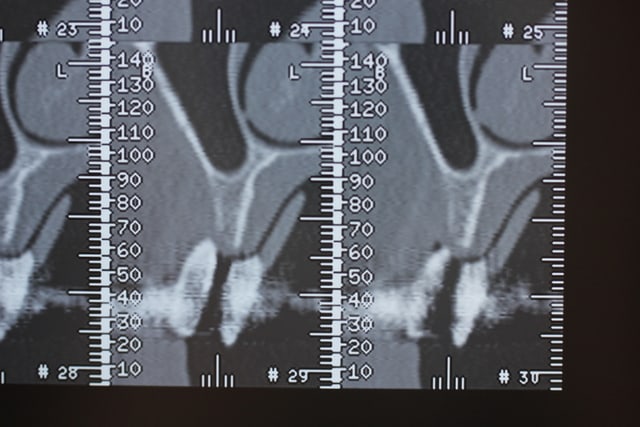

On est en 13 14 15, patiente d'une soixantaine d'années, sans antécédents médicaux ni dentaires. Un peu frileuse pour les grosses chirs mais elle était néanmoins partante pour les implants.

Ce sont les dernières coupes qui correspondent au site de la 13